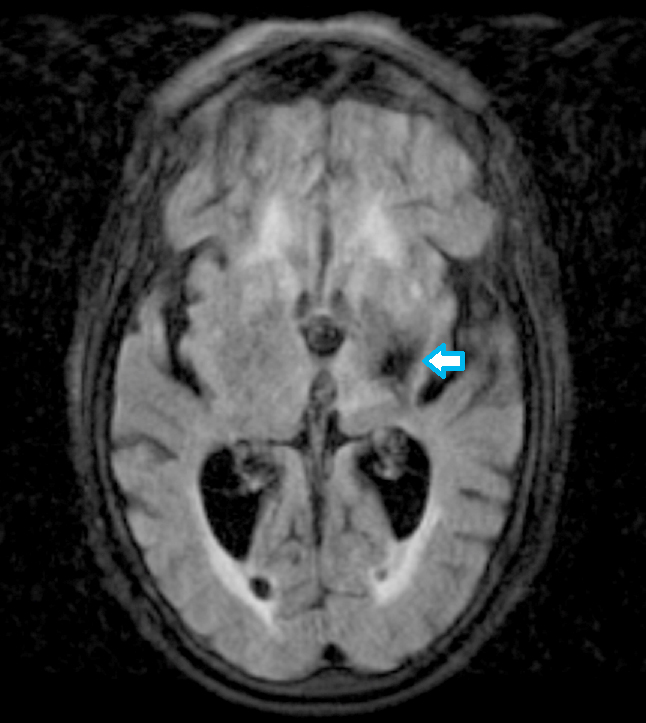

- MRI

- Diffusion weighted MRI: most accurately measures the infarct core (i.e., nonsalvageable tissue) (Radiology 2009;251:627)

Radiology description

- MRI

- Diffusion weighted imaging (DWI): hyperintense signal in the acutely infarcted tissue; low signal on apparent diffusion coefficient (ADC) map

- Infarcts are often T2 hyperintense

- Collateral flow on FLAIR: linear or serpentine hyperintensities distal to the site of obstruction (Neurology 2009;72:1134)

- Perfusion weighted imaging (PWI) - DWI mismatch: used to estimate the salvageable tissue (i.e., penumbra) in acute infarct (Neuroimaging Clin N Am 2021;31:177, AJNR Am J Neuroradiol 2015;36:32)

- Ischemic areas on PWI are compared with areas shown by DWI (i.e., the infarct core or nonsalvageable tissue); the mismatch represents the volume of salvageable tissue with reperfusion therapy

Radiology images